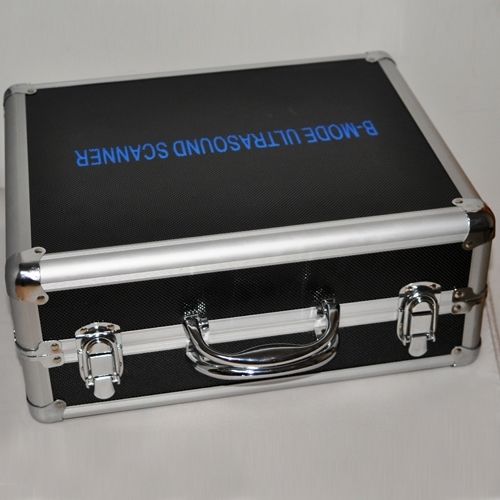

Portability and Convenience

One of the standout features of this ultrasound machine is its portability. The compact design, combined with a carrying case, makes it easy to transport between clinics or even to home visits. This ensures that medical professionals can deliver timely care, regardless of location. Therefore, it’s perfect for practitioners who need versatility in their equipment.